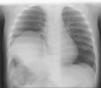

Lactante de 8meses que consulta por asimetría torácica y leve dificultad respiratoria desde hace 2meses. Sin antecedentes perinatales de interés. A la exploración presenta únicamente asimetría torácica con hundimiento de últimas costillas derechas (fig. 1). Se realiza radiografía de tórax, que muestra elevación franca del hemidiafragma derecho (fig. 2) y ecografía torácica que confirma dicha elevación, con diafragma aparentemente íntegro. Finalmente se solicita resonancia magnética torácica secuencia eco de gradiente bajo sedación leve, evidenciándose elevación y adelgazamiento muscular del hemidiafragma derecho, sin solución de continuidad y con movimiento paradójico ipsilateral, compatible con eventración diafragmática congénita (fig. 3). Dado que persiste e incluso aumenta la dificultad respiratoria, se decide intervención quirúrgica mediante plicatura diafragmática, con evolución favorable, permaneciendo el paciente asintomático hasta la actualidad.